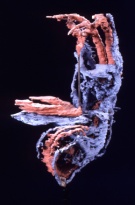

Preparation for microscopic examination

Whole Embryo